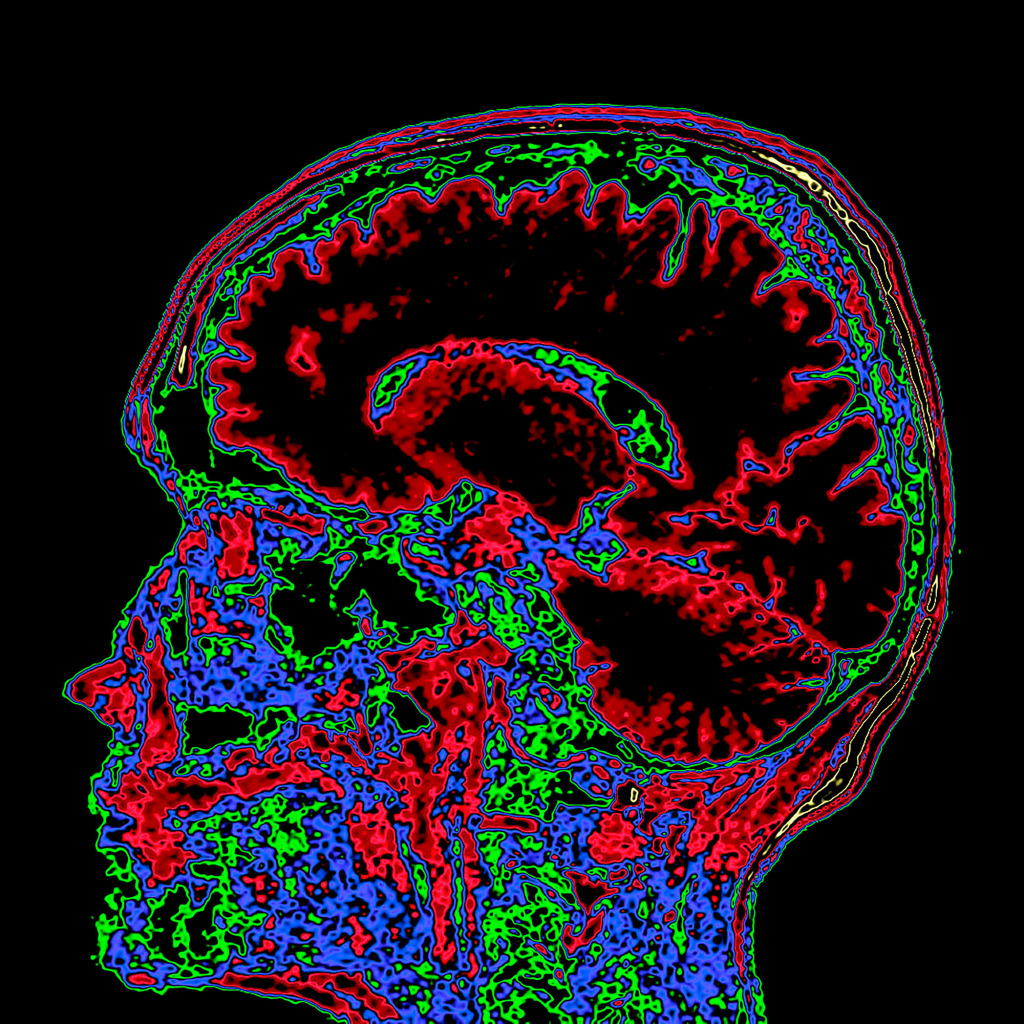

Most of the time, radiologists work with black and white images.

A multi-coloured, bright image is a way to shift the gaze and perceive things differently.

Also, I like to experiment with different photo filters and settings.

The program for processing radiological images (DICOM archives) allows you to create and look at a three-dimensional image from different angles.

If you change the location of the virtual lens, thereby changing the perspective, you can get such images.

I simply create a table where the radiological density of the material can correspond to any colour.

After combining different shades, I only have to choose what I like the most.